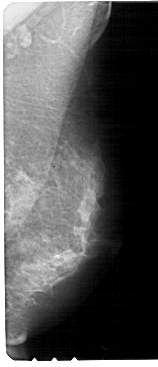

A_1238_1.LEFT_CC

LEFT_CC LINES 5491 PIXELS_PER_LINE 2281 BITS_PER_PIXEL 12 RESOLUTION 43.5 OVERLAY

FILE: A_1238_1.LEFT_CC.OVERLAY

TOTAL_ABNORMALITIES 1

ABNORMALITY 1

LESION_TYPE CALCIFICATION TYPE PLEOMORPHIC DISTRIBUTION CLUSTERED

ASSESSMENT 4

SUBTLETY 3

PATHOLOGY MALIGNANT

TOTAL_OUTLINES 1

BOUNDARY